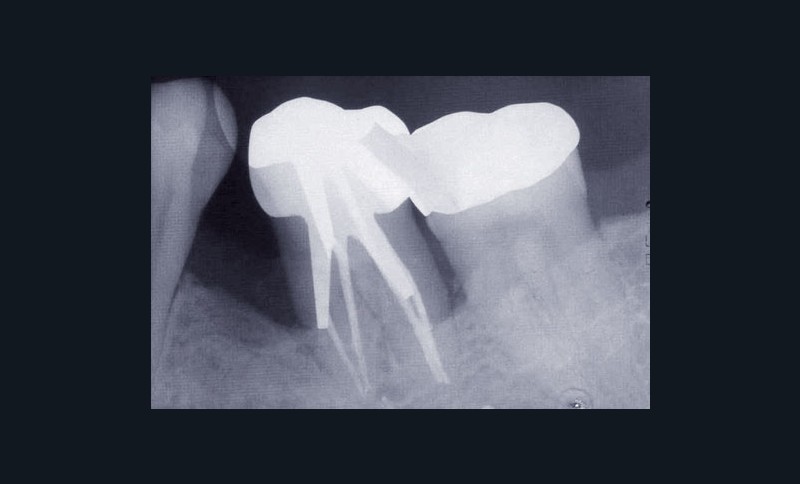

Une patiente âgée de 45 ans consulte à la fin des années 1990 avec une contention en échelle au maxillaire afin de soulager les mobilités des dents antérieures.

Les examens cliniques et radiographiques montrent une parodontite chronique généralisée (fig. 1a à m).

Nous décidons d’entreprendre une thérapeutique initiale parodontale classique dans tous les secteurs, y compris l’extraction de 24, un bridge de 45 à 48 avec 46 en pontique, un bridge complet de contention de 17 à 27 sur 11 piliers dentaires et une greffe épithélio-conjonctive sur 31. Cette dernière ne sera jamais réalisée. Le bridge maxillaire permettra de réduire le surplomb antérieur et d’améliorer le sourire de la patiente, ce qui constitue l’une de ses demandes.